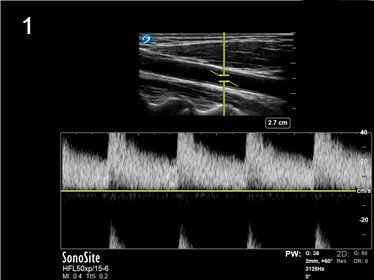

Aliasing Artifact Image